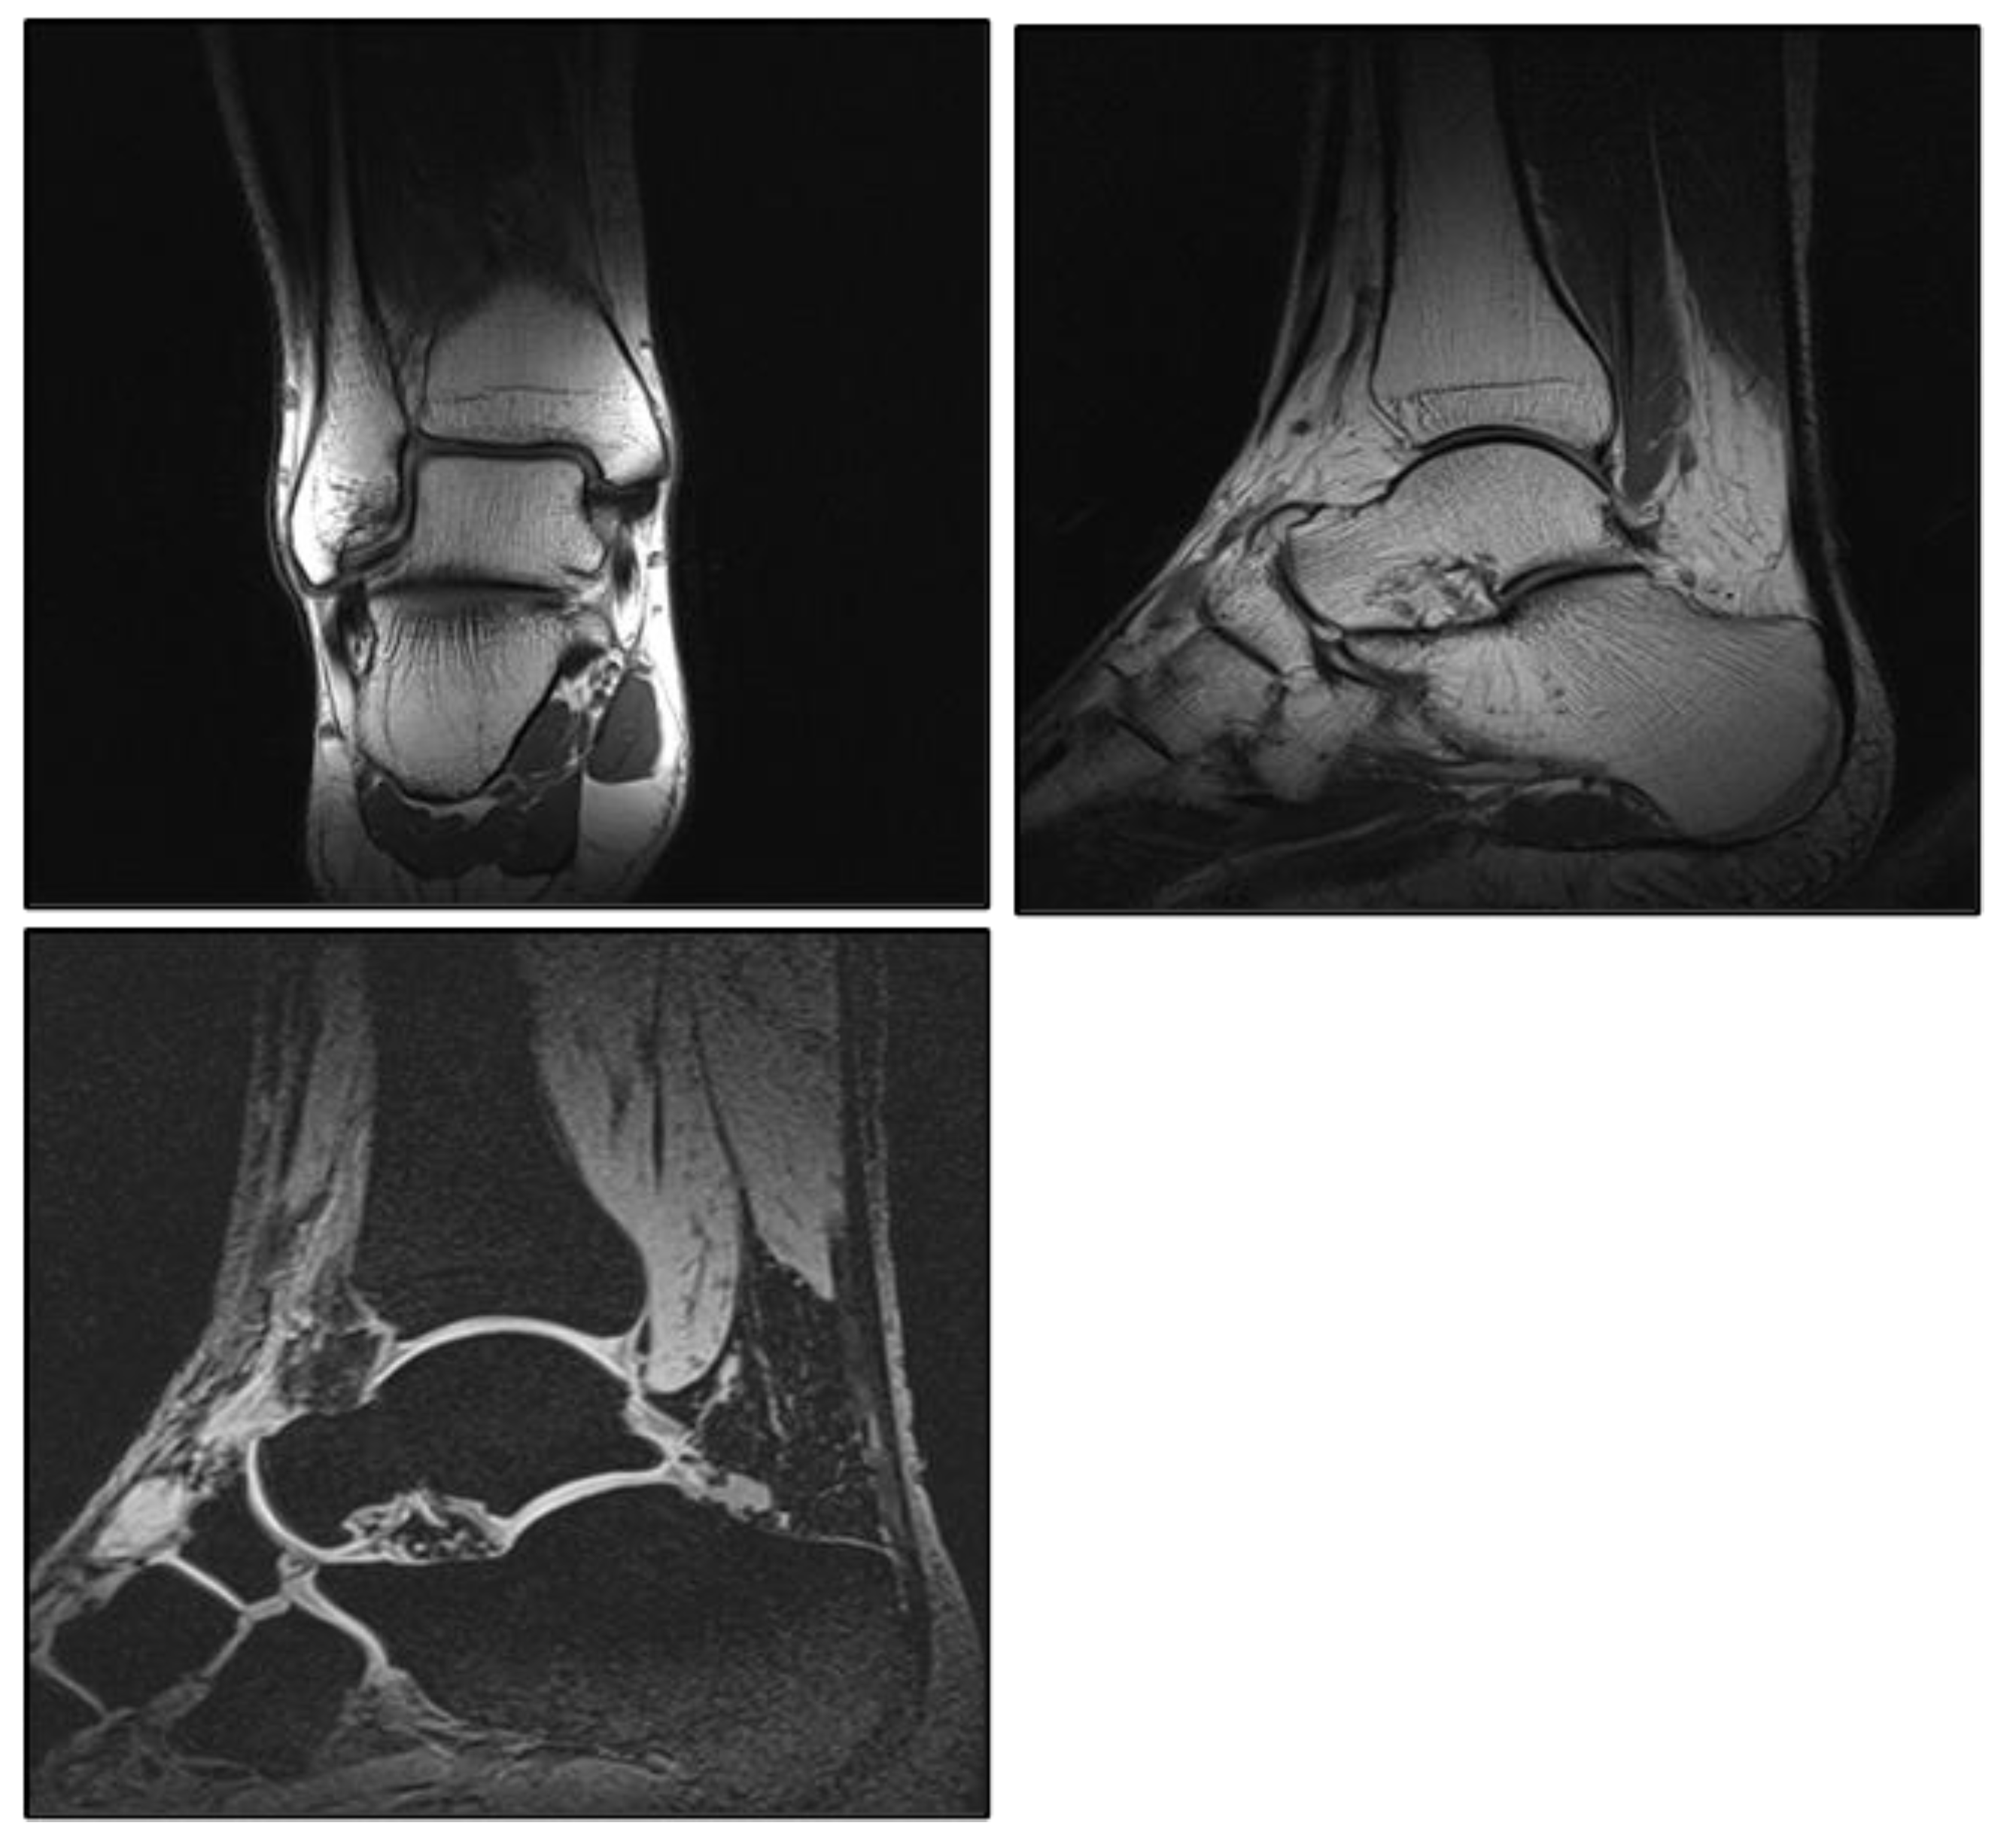

Figure A4.

Image examples of coronal and sagittal PD sequences and sagittal VIBE sequence.